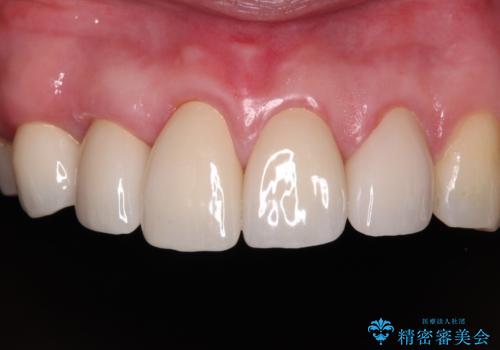

また、当初は予定しておりませんでしたが、歯列が整ったことで前歯の歯の色や形が気になり、矯正治療後にオールセラミッククラウンにて補綴治療することとしました。

あっという間に気になっていた歯列が改善され、自然な口元になり、患者様には大変満足していただきました。